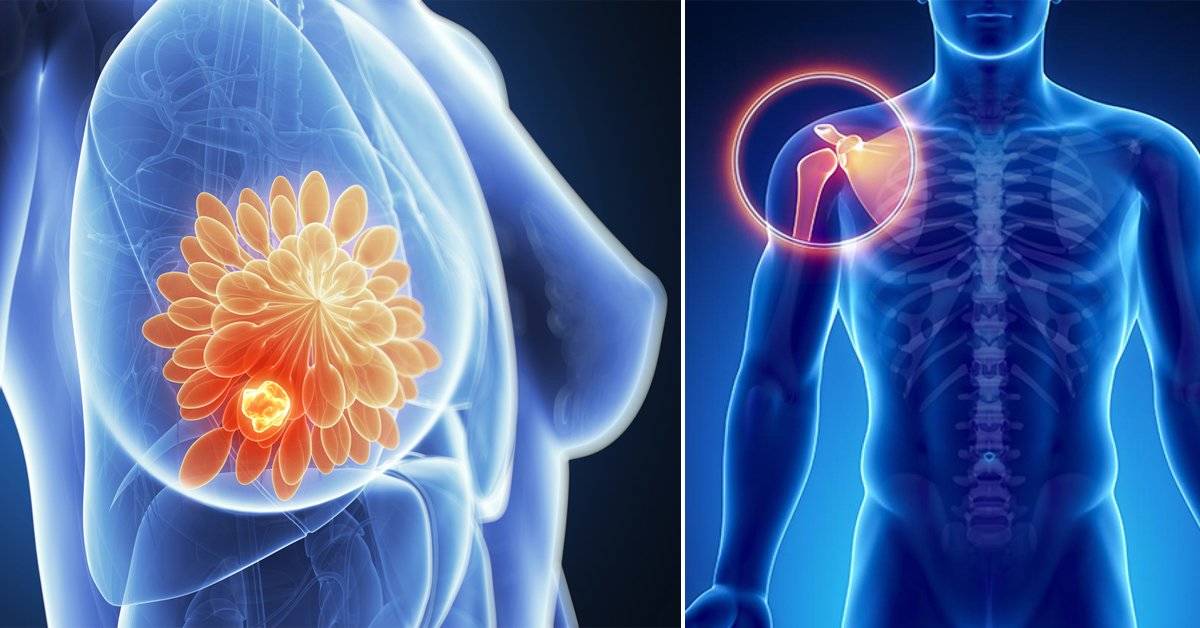

que es un sarcoma abdominal Un sarcoma es un tumor maligno raro, que se desarrolla en el tejido conjuntivo, tejido de conexión de los órganos y evoluciona rápidamente por todo el organismo. El primer signo de un sarcoma en un brazo, una pierna o el tronco puede ser un bulto o hinchazón sin dolor. El sarcoma de tejido blando es una enfermedad por la que se forman células malignas (cancerosas) en los tejidos blandos del cuerpo. El sarcoma de tejido blando es un tipo de cáncer poco frecuente que comienza en los tejidos que conectan, sostienen y recubren otras estructuras del. El liposarcoma puede producirse en las células grasas de cualquier parte del cuerpo, pero,. El rabdomiosarcoma (rms) es un tipo raro de cáncer que se forma en el tejido blando, específicamente en el tejido muscular del esqueleto o, a veces, en. Es posible que ciertos trastornos. Se conoce como sarcoma a un grupo de cánceres cuyo origen se encuentra en las células del tejido conjuntivo, el cual conforma la estructura del cuerpo humano.

cáncer de tejidos blandos en adultos